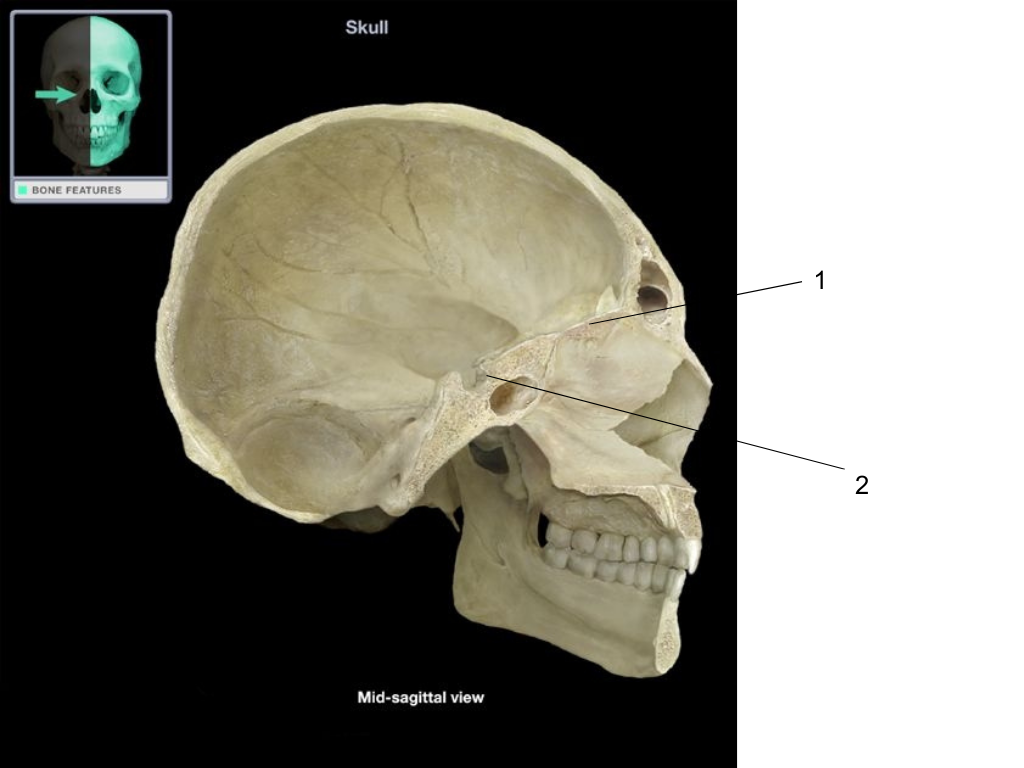

cribiform plate of ethmoid

what is #1 pointing at?

sella turcica of sphenoid

what is #2 pointing at?